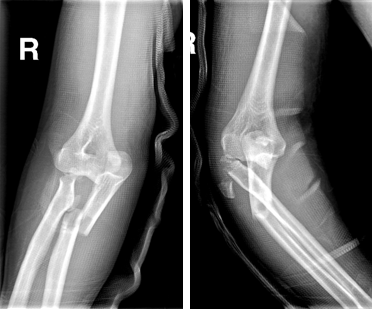

男性,22岁,摔伤致右肱骨髁间骨折

术前

术后